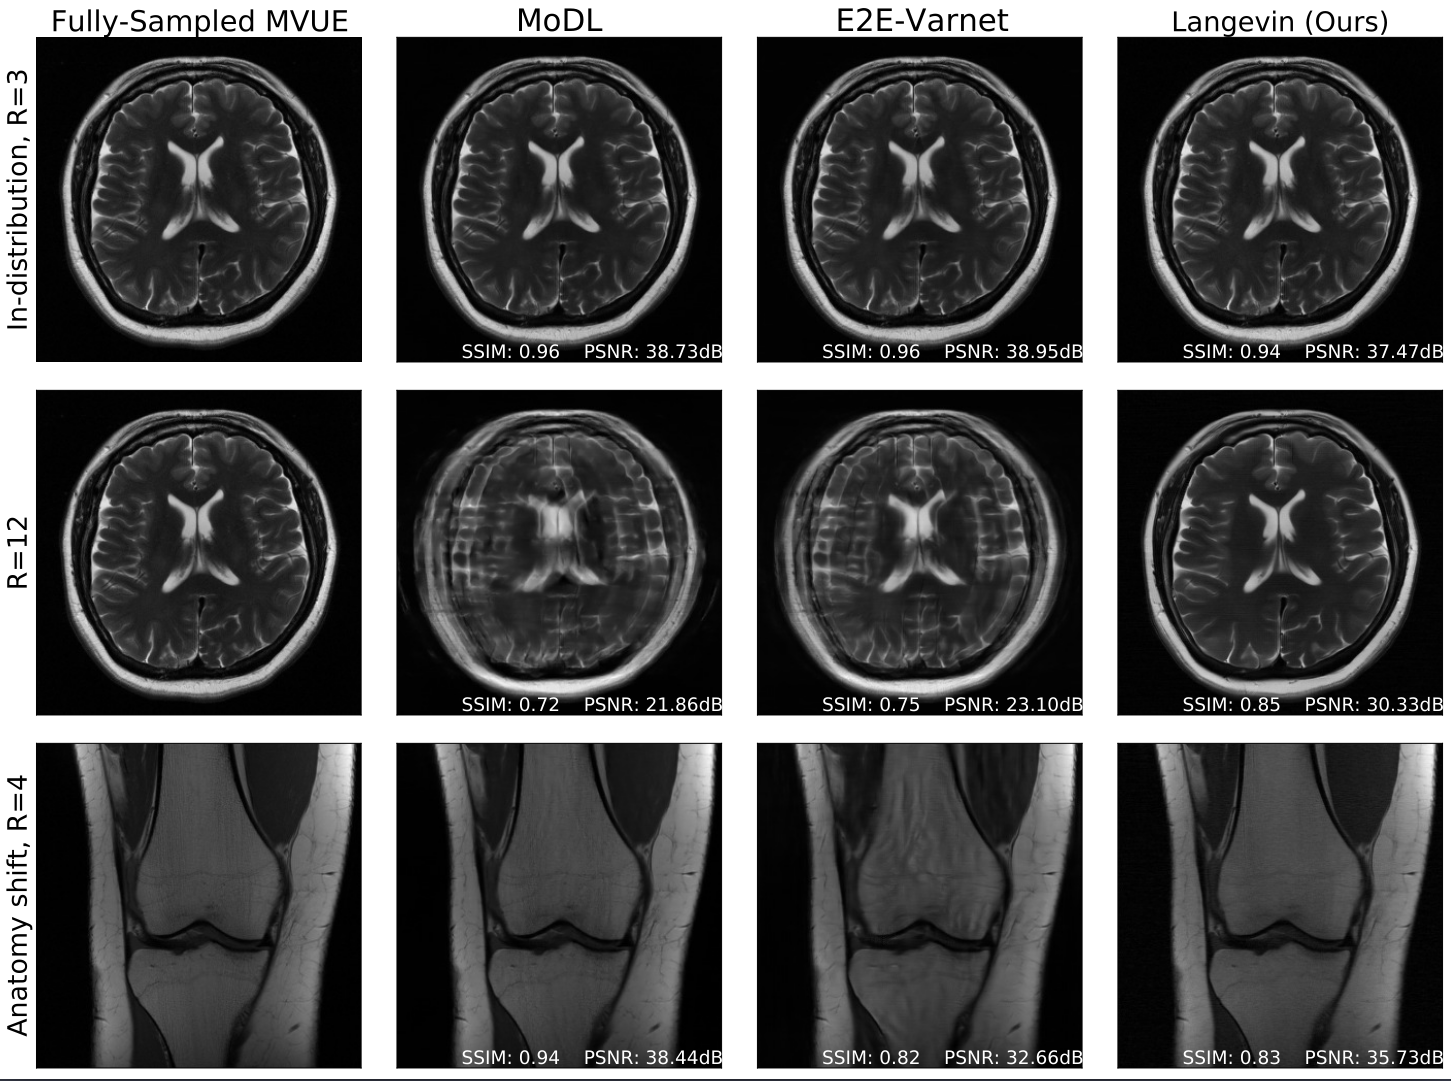

Ajil Jalal, Marius Arvinte, Giannis Daras, Eric Price, Alex Dimakis, Jon Tamir

Thirty-Fifth Conference on Neural Information Processing Systems (NeurIPS) 2021

The CSGM framework (Bora-Jalal-Price-Dimakis' 17) has shown that deep generative priors can be powerful tools for solving inverse problems. However, to date this framework has been empirically successful only on certain datasets (for example, human faces and MNIST digits), and it is known to perform poorly on out-of-distribution samples. In this paper, we present the first successful application of the CSGM framework on clinical MRI data. We train a generative prior on brain scans from the fastMRI dataset, and show that posterior sampling via Langevin dynamics achieves high quality reconstructions. Furthermore, our experiments and theory show that posterior sampling is robust to changes in the ground-truth distribution and measurement process.